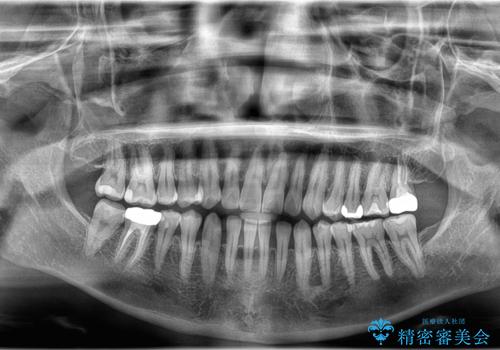

- すきっ歯と切端咬合(上下の前歯が先端で当たるかみ合わせ)を主訴にご来院された患者様です。

矯正検査を行った結果、非抜歯でインビザラインによる治療が可能と判断し、マウスピース矯正で改善を行いました。

11ヵ月で矯正治療が終了し、前歯の隙間も改善、見た目とかみ合わせも良好な状態となり、患者様にも大変ご満足いただけました。